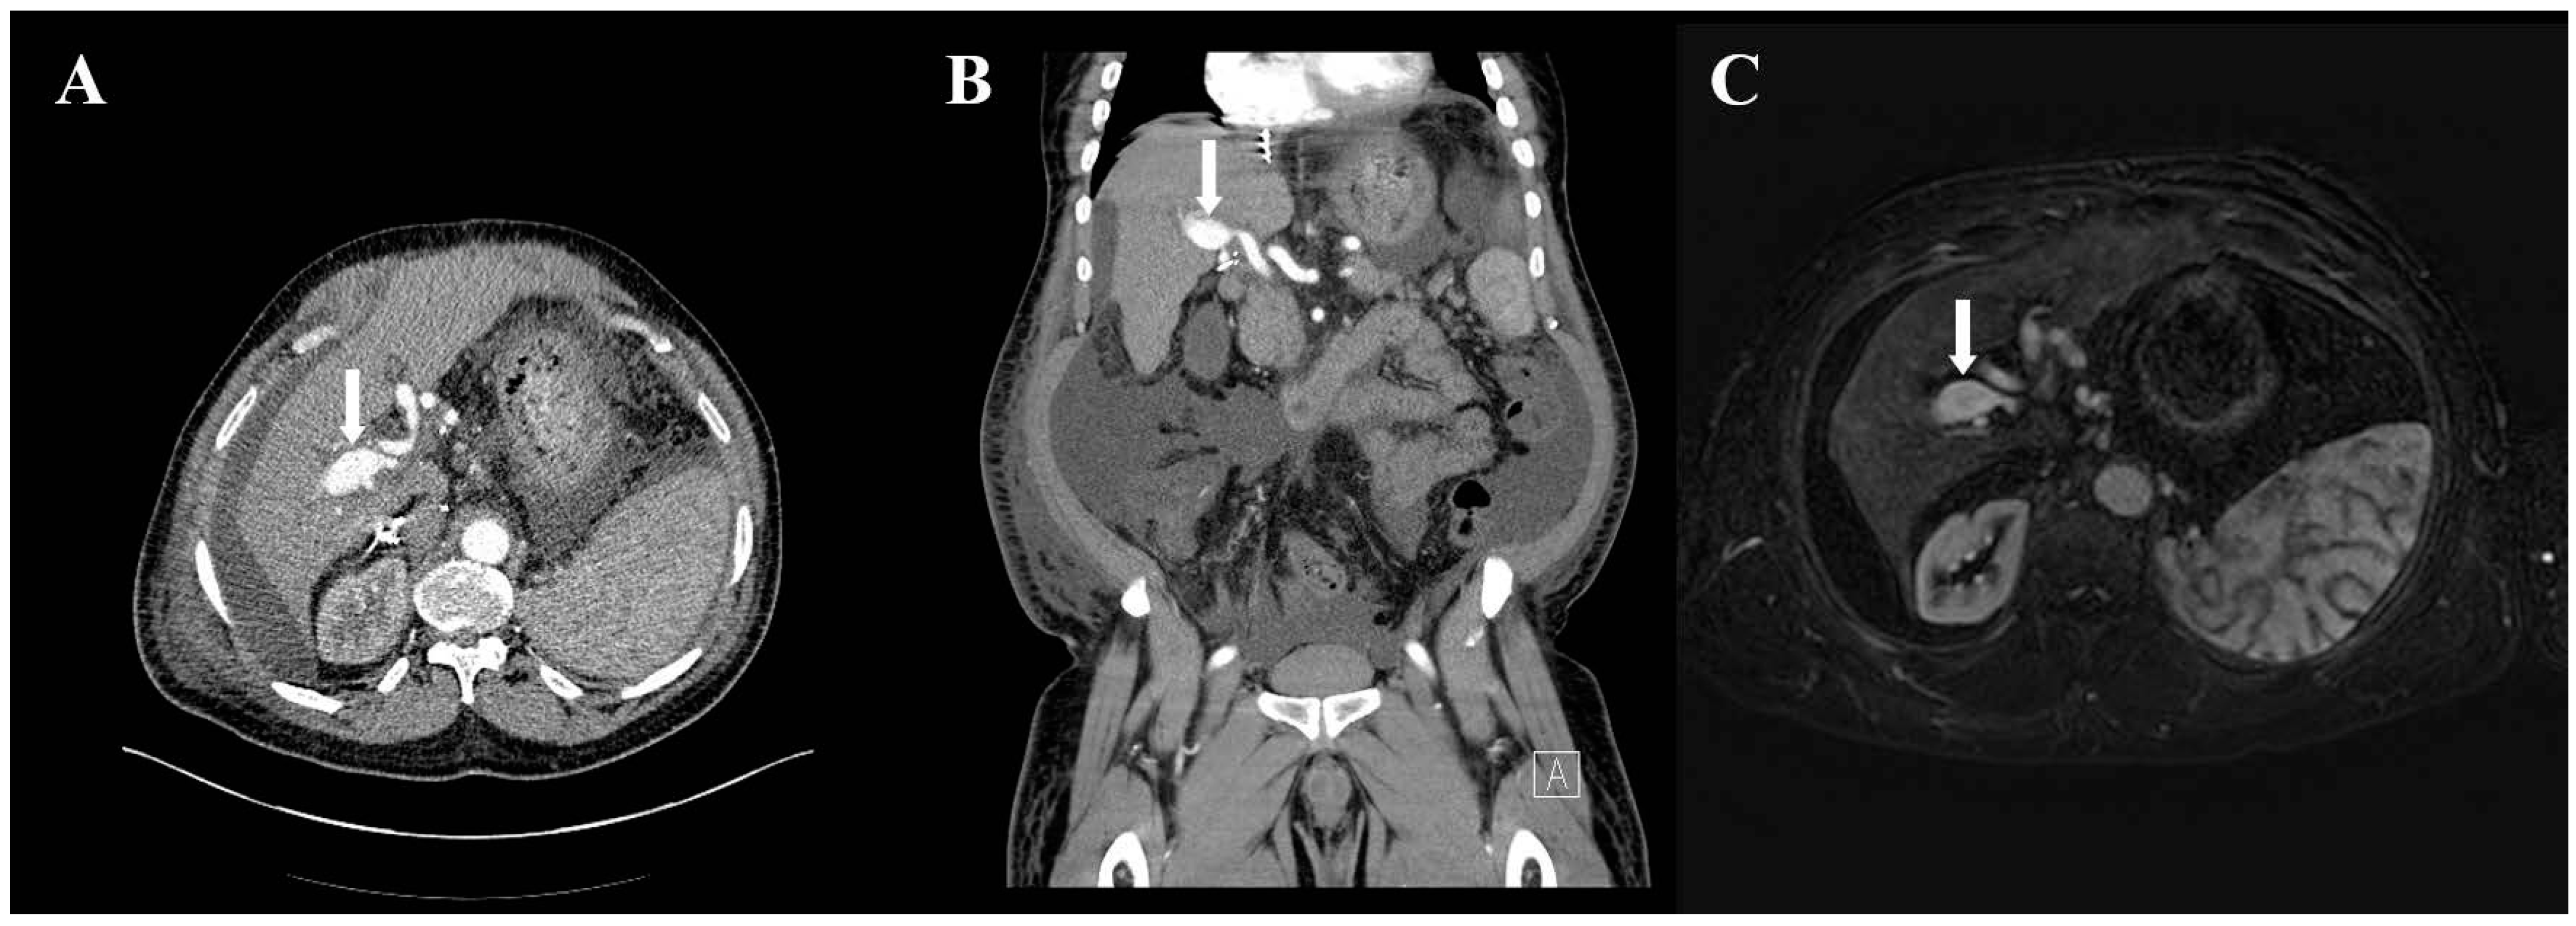

A 65-year-old man with a history of orthotopic liver transplant 5 years prior and recurrent hepatitis C-related cirrhosis had an incidental finding of HAPVF after presenting with abdominal pain and distention due to large volume ascites. Abdominal computed tomography with intravenous contrast described a tortuous hepatic artery with the early opacification of the main portal vein on arterial phase imaging (Figure 1), suggestive of HAPVF. The left portal vein was thought to be thrombosed due to its absence on the scan. Numerous varices and massive ascites were also noted.

Figure 1. Intrahepatic communication between hepatic artery and portal vein. (A) Contrast-enhanced axial computed tomography of the abdomen demonstrating early opacification of the dilated portal vein on arterial phase (arrow). (B) Contrast-enhanced coronal computed tomography of the abdomen demonstrating early opacification of the dilated portal vein on arterial phase (arrow). (C) Contrast-enhanced magnetic resonance imaging of the abdomen demonstrating early opacification of the portal vein on arterial phase (arrow).